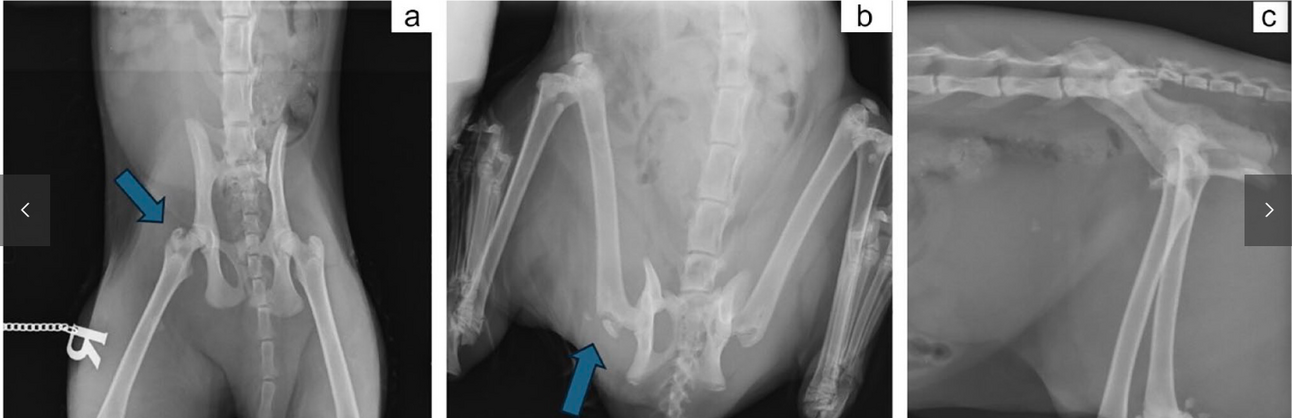

Feline Trochanter Fractures: Rare, Traumatic, and Often Missed on Standard Radiographs

Journal of Feline Medicine and Surgery 2025